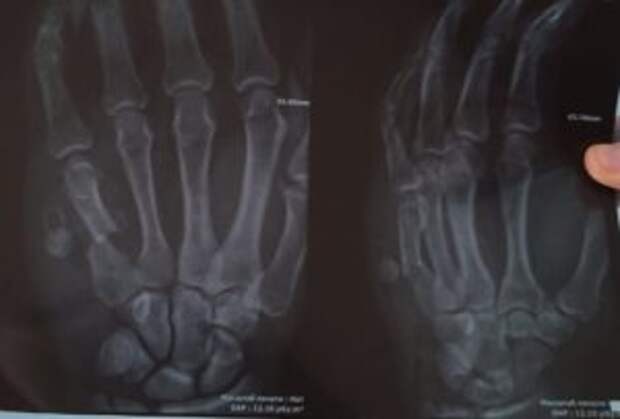

Diagnóstico: Fractura por arma de fuego del quinto metacarpiano con desplazamiento. Se ha formado una articulación falsa, se requiere fusión ósea.